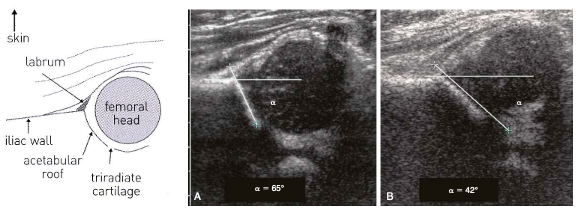

• 초음파: ilium과 acetabulum의 bony roof 가 이루는 각도를 측정 → 60도 이상이 정상